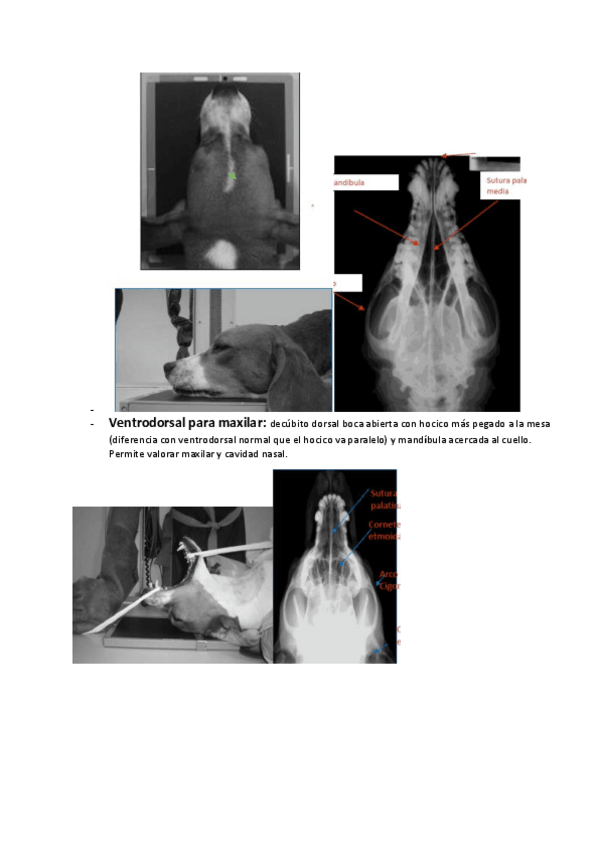

He publicado nuevos apuntes de 3º Diagnóstico Por la Imagen: rx-en-peq-anim.pdf

24 páginas